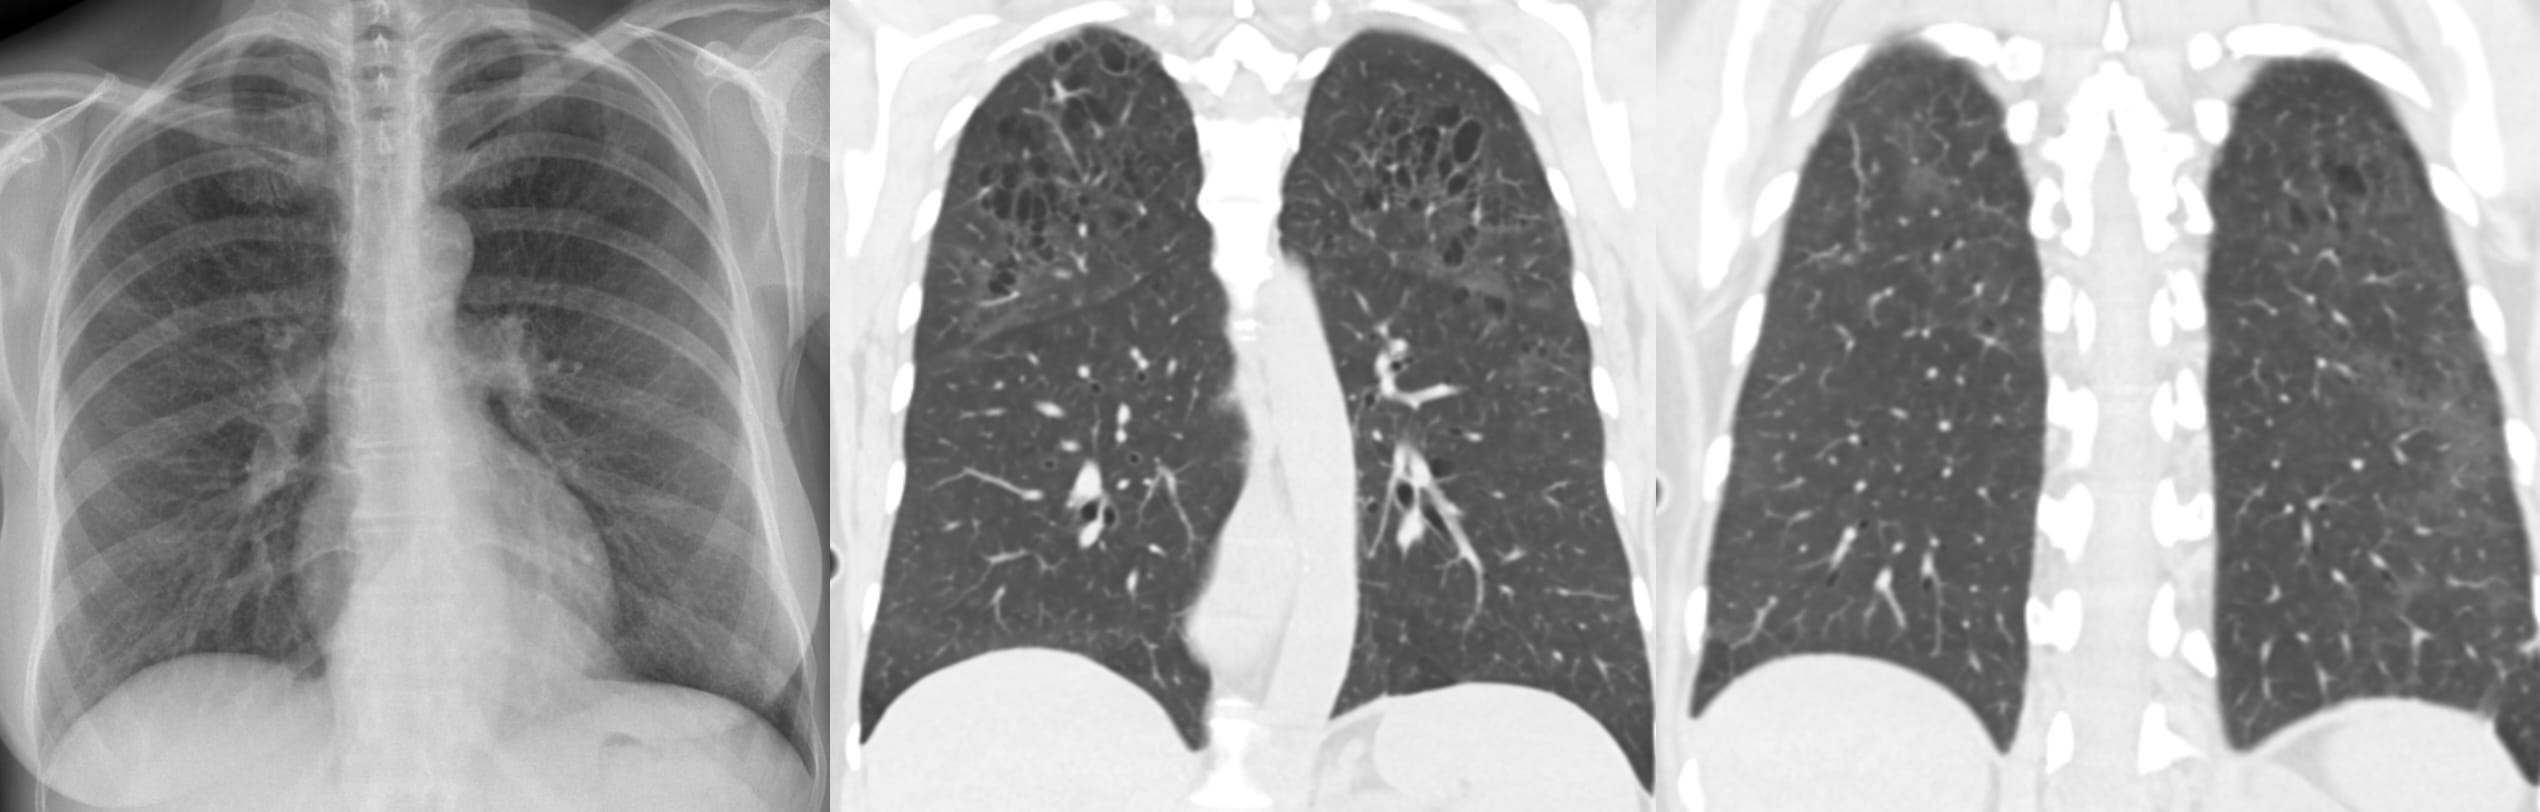

Key Points

Note the predominant involvement of the upper lungs.

The very definition of an Aunt Minnie